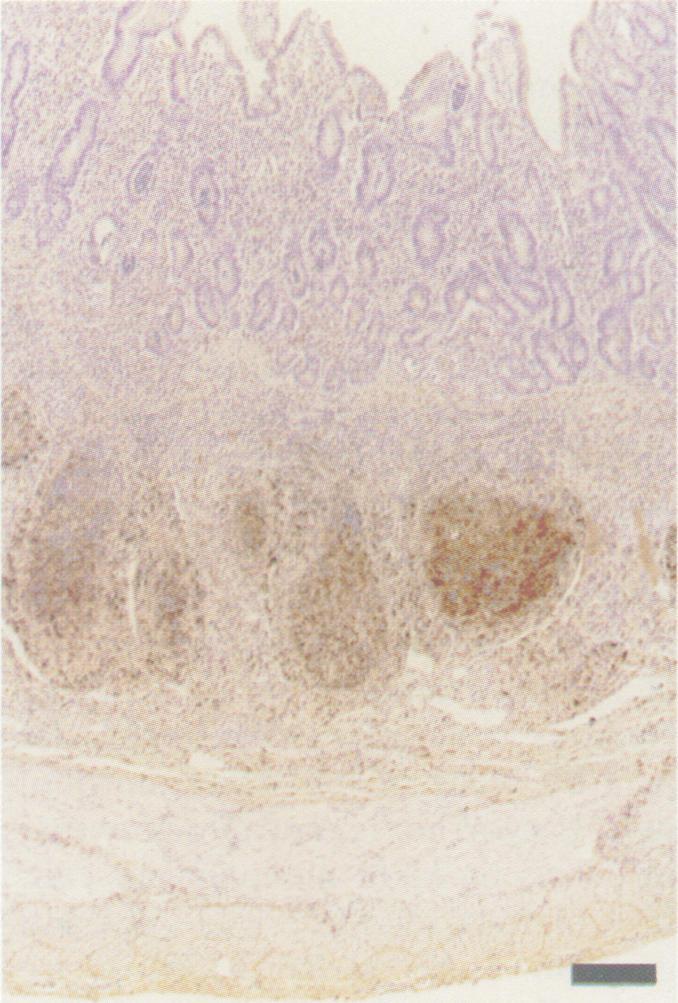

During the past several years, acute infections with bovine viral diarrhea virus (BVDV) have been causally linked to hemorrhagic and acute mucosal disease-like syndromes with high mortality. The majority of BVDVs isolated in such cases have been classified as type II on the basis of genetic and antigenic characteristics. It was our objective to examine clinical disease, lesions and potential sites of viral replication, following experimental BVDV type II infection in young calves. On approximately day 35 after birth, calves that had received BVDV-antibody-negative colostrum were infected by intranasal inoculation of 5 x 10(5) TCID50 of BVDV type II isolate 24,515 in 5 mL of tissue culture fluid (2.5 mL/nostril). Calves were monitored twice daily for signs of clinical disease. Approximately 48-72 h after infection, all calves developed transient pyrexia (39.4-40.5 degrees C) and leukopenia. Beginning on approximately day 7 after infection, all calves developed watery diarrhea, pyrexia (40.5-41.6 degrees C), marked leukopenia (> or = 75% drop from preinoculation values), variable thrombocytopenia, and moderate to severe depression. Calves were euthanized on days 10, 11, or 12 after infection due to severe disease. Gross and histological lesions consisted of multifocal bronchointerstitial pneumonia (involving 10%-25% of affected lungs), bone marrow hypoplasia and necrosis, and minimal erosive lesions in the alimentary tract. Immunohistochemical staining for BVDV revealed widespread viral antigen usually within epithelial cells, smooth muscle cells and mononuclear phagocytes in multiple organs, including lung, Peyer's patches, gastric mucosa, thymus, adrenal gland, spleen, lymph nodes, bone marrow, and skin. This BVDV type II isolate caused rapidly progressive, severe multisystemic disease in seronegative calves that was associated with widespread distribution of viral antigen and few gross or histological inflammatory lesions.

在过去几年中,牛病毒性腹泻病毒(BVDV)急性感染与高死亡率的出血性及急性黏膜病样综合征存在因果关联。在此类病例中分离出的大多数BVDV,根据遗传和抗原特性被归类为II型。我们的目的是在幼龄犊牛经实验性感染II型BVDV后,检查其临床疾病、病变以及病毒复制的潜在部位。出生后约35天,接受了BVDV抗体阴性初乳的犊牛通过鼻内接种5 mL组织培养液(每侧鼻孔2.5 mL)中的5×10⁵ TCID₅₀ II型BVDV分离株24,515进行感染。每天对犊牛监测两次临床疾病体征。感染后约48 - 72小时,所有犊牛出现短暂发热(39.4 - 40.5摄氏度)和白细胞减少。从感染后约第7天开始,所有犊牛出现水样腹泻、发热(40.5 - 41.6摄氏度)、显著白细胞减少(较接种前值下降≥75%)、可变的血小板减少以及中度至重度抑郁。由于严重疾病,犊牛在感染后第10、11或12天实施安乐死。大体和组织学病变包括多灶性支气管间质性肺炎(累及10% - 25%的患肺)、骨髓发育不全和坏死,以及消化道的轻微糜烂性病变。对BVDV进行免疫组织化学染色显示,病毒抗原广泛存在于多个器官的上皮细胞、平滑肌细胞和单核吞噬细胞内,包括肺、派伊尔氏淋巴集结、胃黏膜、胸腺、肾上腺、脾脏、淋巴结、骨髓和皮肤。这种II型BVDV分离株在血清阴性犊牛中引起迅速进展的严重多系统疾病,这与病毒抗原的广泛分布以及极少的大体或组织学炎症病变相关。